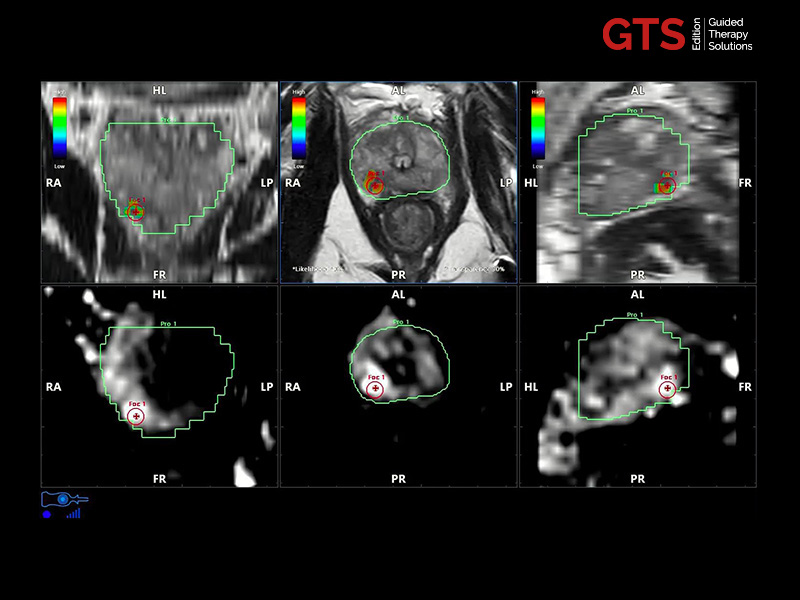

Expert users and beginners can now achieve a heightened degree of simplicity and precision by using UroFusion, Esaote’s cutting-edge fusion imaging solution that makes the most of the combination of US and MR or PET modalities.

By harnessing Augmented Insight™ (A.I.) technology, our dedicated solution enhances workflow efficiency by Automating MR Prostate Contouring & Segmentation with instant and automatic US-MR Synchronization, applied to both transperineal (TPUS) and transrectal (TRUS) prostate biopsy approaches.

Using UroFusion, clinicians will benefit from our intuitive tools to fasten the fusion procedures: the automatic prostate contouring and biopsy sample mapping are certainly the most impressive.

UroFusion seamlessly offers the ability to combine different mpMRI series, facilitating the identification of suspicious prostate lesions.

mpMRI targeting phase of PI-RADS 5 peripheral lesion